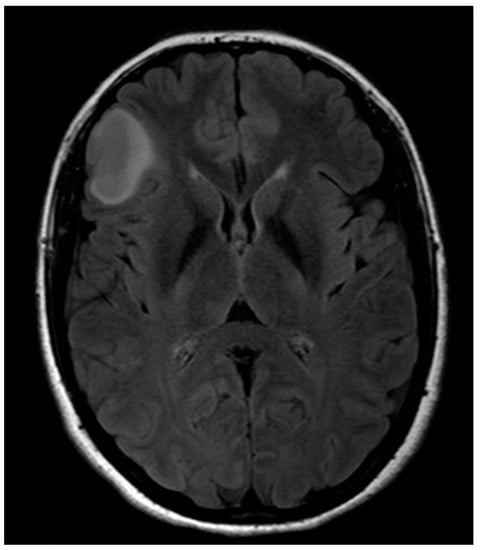

A 32-year-old left-handed female patient was referred to our department with an MR scan showing a right fronto-opercular diffuse low-grade glioma and performed as a diagnostic work-up for headache (Figure 1). Left-handedness was confirmed with Edinburgh’s inventory. She had no preoperative language disorders.

Figure 1. Anatomical MRI scan showing right fronto-opercular diffuse low-grade glioma.